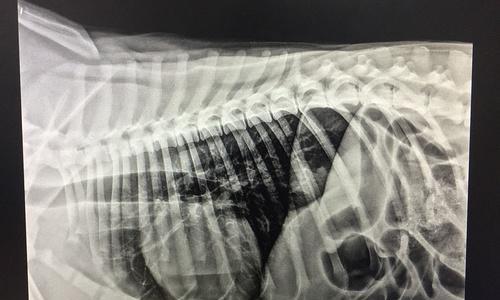

狗肠梗阻是一种常见的狗病,如果不及时处理,可能会导致严重的并发症甚至危及生命。手术是治疗狗肠梗阻的一种有效方法,但手术后的恢复期和影响因素却鲜为人知。本文旨在介绍狗肠梗阻手术后的恢复情况,以及一些关键因素,帮助宠物主人更好地护理自己的宠物。